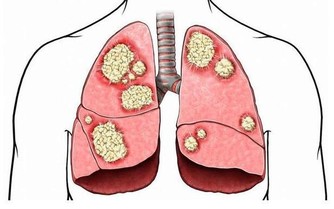

研究顯示,我國腎病患者呈逐年增加的趨勢,很大一部分和藥物使用不當有關。

一旦發生藥源性腎損傷,輕則損傷腎功能,導致腎炎;重則導致腎壞死、急性或慢性腎功能衰竭,

過多服用喹諾酮類藥物、氨基糖苷類抗生素及中草藥,都可能對腎臟造成損傷,甚至導致腎衰竭。